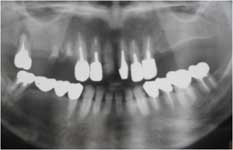

両上顎臼歯部及び右下臼歯部欠損症例、X-ray写真

術前